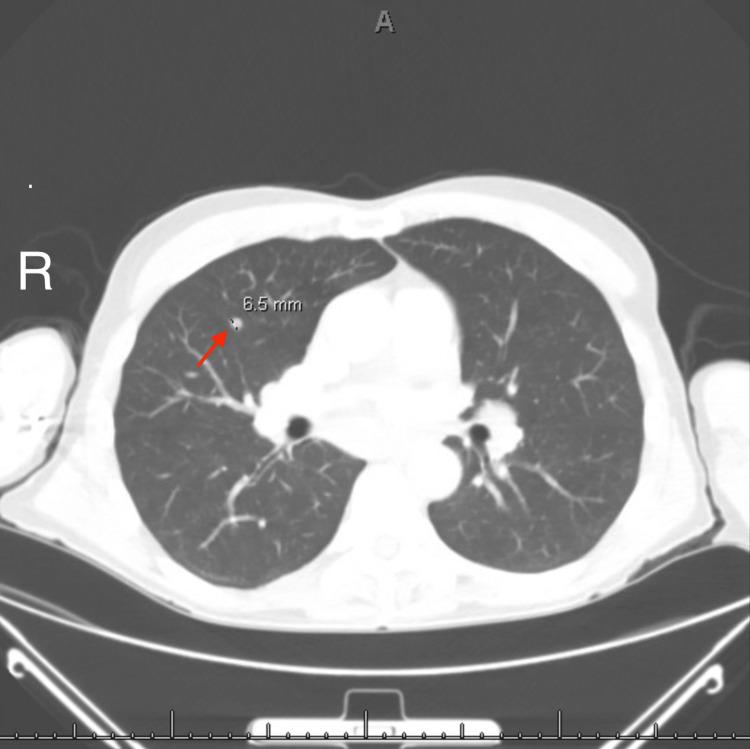

Sarcoidosis is a multisystem granulomatous disorder with an unknown etiology that typically involves the lungs, skin, and lymph nodes, with neurological involvement being relatively rare. We discuss a case of neurosarcoidosis in a 64-year-old man who initially presented with unexplained cognitive impairment, insomnia, hyponatremia, paresthesias, and weight loss and later developed uveitis, diplopia, and dysphagia. Ultimately, findings of hilar and mediastinal lymphadenopathy on chest computed tomography (CT) resulted in bronchoscopy, which led to the diagnosis. This case highlights a rare presentation of sarcoidosis with an unusual constellation of symptoms. We discuss the difficulty involved in diagnosing this disorder as well as its highly variable course.

结节病是一种病因不明的多系统肉芽肿性疾病,通常累及肺部、皮肤和淋巴结,神经系统受累相对少见。我们讨论一例64岁男性神经结节病病例,该患者最初表现为不明原因的认知障碍、失眠、低钠血症、感觉异常和体重减轻,后来出现葡萄膜炎、复视和吞咽困难。最终,胸部计算机断层扫描(CT)显示肺门和纵隔淋巴结肿大,进而进行了支气管镜检查,从而确诊。该病例突出了结节病一种罕见的表现形式,伴有一系列不寻常的症状。我们讨论了诊断这种疾病的困难以及其高度多变的病程。